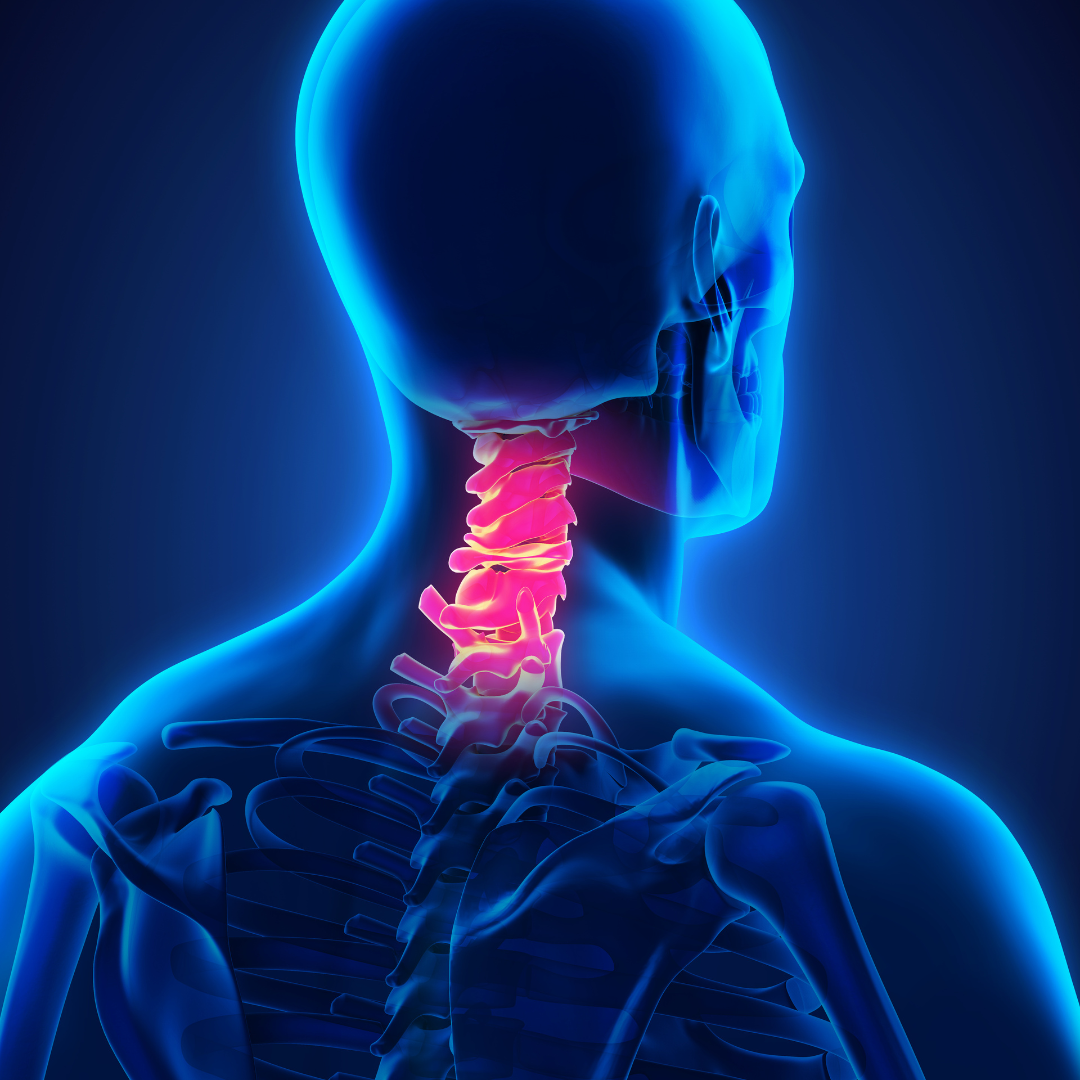

- Disk rupture or herniation - Occurs when the soft, gel-like center of a spinal disk pushes through a crack in the tougher exterior casing. This condition can press on spinal nerves, leading to pain, numbness, or weakness in an arm or leg. It often results from wear and tear or a sudden injury.

- Spinal cord or traumatic brain injuries (TBI) - Damage to the spinal cord that can result in a loss of function, such as mobility or feeling. It often leads to permanent changes in strength, sensation, and other body functions below the site of the injury. A TBI is a disruption in the normal function of the brain caused by a blow, bump, or jolt to the head or penetrating head injury. Symptoms can range from mild (temporary confusion) to severe (extended periods of unconsciousness or amnesia).

- Whiplash - A neck injury caused by a sudden, forceful back-and-forth

movement of the neck, typically occurring in rear-end car accidents. Symptoms include neck pain, stiffness, headaches, and sometimes dizziness or blurred vision.

movement of the neck, typically occurring in rear-end car accidents. Symptoms include neck pain, stiffness, headaches, and sometimes dizziness or blurred vision.